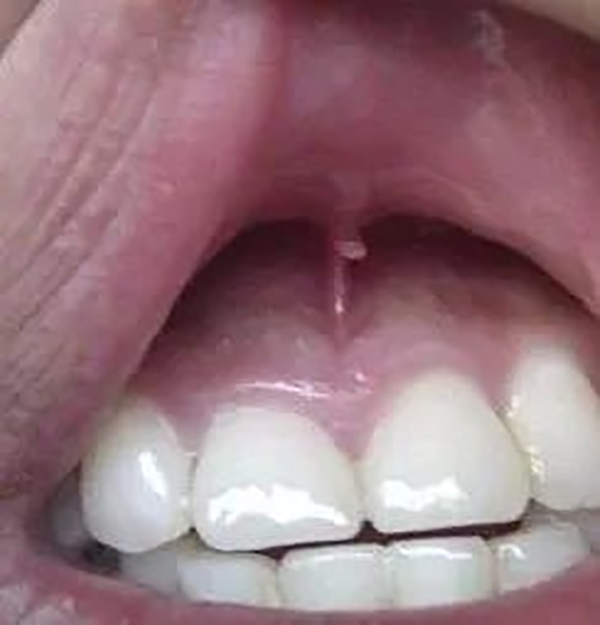

接下来查看上唇系带的断裂程度。可以用医用棉签轻轻挑起上唇观察。若伤口不是很大(图2),则用医用生理盐水给宝宝漱口或者用棉签擦拭。此步骤主要是消毒,防止伤口感染。此外,每天可以用盐水漱口,或者碘伏棉签擦拭受伤处,还要注意多喝水,以清洁伤口。这种情况不需要去医院,等待伤口自行愈合就可以,一般需要7-10天。

图2 上唇系带的轻微断裂(图片来源于网络)